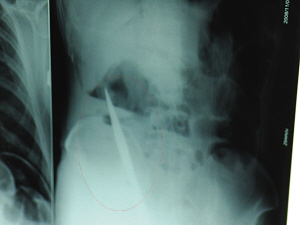

X光片上,尖刀清晰可見。

從男子體內(nèi)取出的尖刀足足有19厘米長。

銅山一58歲男子因服毒被送到醫(yī)院搶救,可醫(yī)生采取搶救措施后卻發(fā)現(xiàn)效果不佳。后來經(jīng)細(xì)致檢查,醫(yī)生有了個驚人的發(fā)現(xiàn),該男子的體內(nèi)竟然有一把尖刀,醫(yī)生通過手術(shù)將位于其腹部右側(cè)橫結(jié)腸下緣的尖刀取了出來。這把尖刀足足有19厘米長!據(jù)醫(yī)生推測,這把刀應(yīng)該是從肛門推進(jìn)體內(nèi)的,不知男子為何想以如此殘酷的方式結(jié)束自己生命。由于搶救及時,該男子已暫時脫離危險(xiǎn)。

6日上午,記者在徐州礦務(wù)集團(tuán)總醫(yī)院重癥監(jiān)護(hù)室見到了這名男子,目前他雖然已經(jīng)恢復(fù)了意識,但還不能開口說話,需要呼吸機(jī)輔助呼吸。據(jù)醫(yī)生介紹,4日中午12時左右,這名男子因服毒輕生被緊急送到醫(yī)院進(jìn)行搶救,之前,這名男子已經(jīng)在當(dāng)?shù)剜l(xiāng)鎮(zhèn)醫(yī)院進(jìn)行了近20小時的治療,但效果不佳。“病人被轉(zhuǎn)院到礦總院時已神志不清,血壓極低,處于休克狀態(tài)。”救護(hù)人員給男子洗胃、初步處理以后,發(fā)現(xiàn)男子呼吸急促,于是趕緊給他拍片檢查。結(jié)果讓所有的醫(yī)生大吃一驚,竟有一把尖狀異物橫在該男子腹腔內(nèi)!當(dāng)天下午5時30分,輕生男子被推上了手術(shù)臺。經(jīng)過40多分鐘的手術(shù),該男子腹腔被打開,手術(shù)醫(yī)生發(fā)現(xiàn),男子體內(nèi)的金屬狀異物竟然是一把長19厘米的尖刀!

醫(yī)生告訴記者,手術(shù)后,醫(yī)生在病人身上并未發(fā)現(xiàn)刀痕,最后,經(jīng)過檢查發(fā)現(xiàn),在該男子直腸處找到穿孔。醫(yī)生從醫(yī)學(xué)角度分析后認(rèn)為,這把尖刀應(yīng)該是從肛門插入直腸的。醫(yī)生說,因?yàn)椴∪藫尵燃皶r,尖刀并未傷及要害,所以暫時保住了性命,但后期可能會出現(xiàn)腹腔感染、AIDS、器官衰竭等多種并發(fā)癥。